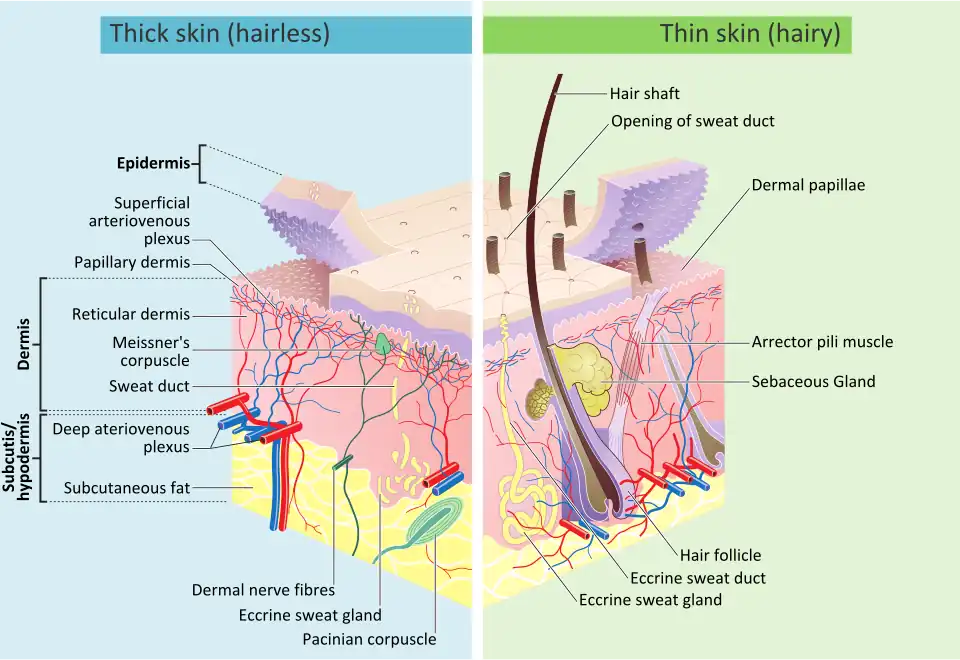

Integumentary system

The integumentary system consists of the covering of the body (the skin), including hair and nails as well as other functionally important structures such as the sweat glands and sebaceous glands. The skin provides containment, structure, and protection for other organs, and serves as a major sensory interface with the outside world.[32][33]